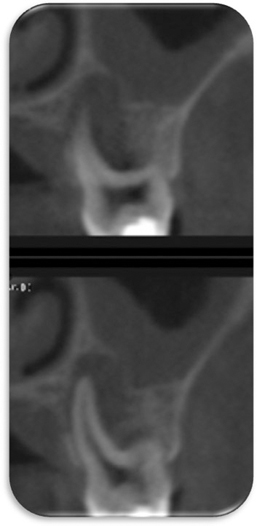

Figure 3

Pre-operative conebeam CT image. CT, computed tomograph.

Figure 4

Figure 3 Pre-operative conebeam CT image. CT, computed tomograph.

Figure 4 Pre-operative conebeam CT image. CT, computed tomograph.